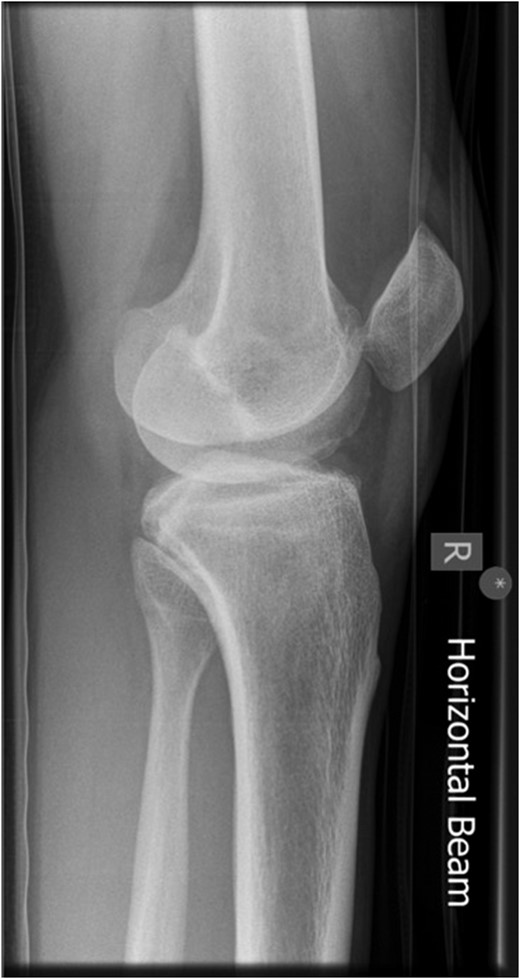

Superior patellar dislocation is a very rare pathology, which happens in middle age. We report a case of spontaneous superior patellar dislocation, which occurred at 30 years of age. Differential diagnosis is patellar tendon rupture, which could be reliably excluded by clinical examination and radiographs. Reduction manoeuvres should be tried with diluted intra-articular local anaesthetic for hydrodilatation to gain mechanical advantage. Splinting the knee in gentle flexion is recommended if general anaesthetic is employed. Recurrent dislocation or osteochondral fractures warrants surgical treatment.

Because of its biomechanical properties, patellofemoral articulation is one of the most complex joints. Patella is suspended by tendons and stabilized by ligaments and is prone to dislocate if an imbalance arises [1]. Superior dislocation of patella is a rare condition with sixth decade being the peak age of presentation. In ~20 reported cases the youngest is a 43-year old [2]. We present a case of spontaneous superior dislocation of patella in a 30-year-old male with no obvious patellofemoral arthrosis.

A 30-year-old gentleman woke up with a sudden onset of knee pain. He had never experienced any knee problems in past. The emergency department referred him as a suspected patellar tendon rupture. History, examination and radiographs revealed a characteristic superior patellar dislocation. No obvious generalized ligament laxity, genu recurvatum or patella alta was found. Hydrodilatation of his knee was performed using 10 ml of 0.5% Chirocaine diluted in 20 ml of 0.9% normal saline. Dislocation was reduced successfully with gentle digital manipulation. Full pain free range of motion was demonstrated after reduction. He was discharged home the same day with no recurrence at 6 months.

A thorough history and careful examination is essential for diagnosis. Due to its rarity, the emergency department usually refer this condition as patellar tendon rupture. It is easy to diagnose if clinician is aware and vigilant. Patient will not be able to do a straight leg raise in both conditions, but for different reasons. It is due to pain in superior patellar dislocation, while loss of extensor mechanism continuity is the cause in patellar tendon rupture. Most cases involved trivial or no trauma in superior patellar dislocation, with contraction of quadriceps in extended knee. Superior movement of the patella locks its lower articular margin on upper border of trochlea. The less frequent mechanism is direct impact on patella. In contrast, rupture of patellar tendon requires significant force and often is a consequence of eccentric contraction of quadriceps.

Knee cannot be flexed actively or passively in superior patellar dislocation, which is the most important differentiating point. Patients with patellar tendon rupture generally have less pain, knee can be passively flexed and often a gap is palpable in patellar tendon area. It should not be forgotten that a tense hematoma in tendon gap is possible.